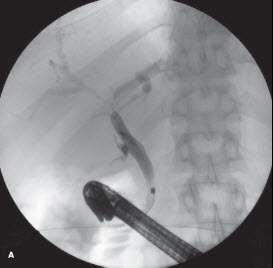

Endoscopic retrograde cholangiopancreatography demonstrated a moderate stricture of the common hepatic duct that extended into the first branches of the intrahepatic ducts. This suggested a possible Bismuth II cholangiocarcinoma (A). A 13-cm 8.5-French plastic stent was placed for decompression. Brushings were negative for malignant cells and tumor markers were also unrevealing. After oncology and surgery consultation, a presumptive diagnosis of cholangiocarcinoma was made. The patient was referred for exploratory laparotomy with the intent of primary resection. Intraoperative choledochoscopy revealed a patent biliary tree with no evidence of cholangiocarcinoma. Instead, an enlarged lymph node on the posterior-medial aspect of the liver was discovered compressing the hilum and causing obstruction. Excisional biopsy results revealed lymphocyte-rich Hodgkin lymphoma (B). A biopsy of concomitant mesenteric lymphadenopathy confirmed the diagnosis.

In Figure A, further biliary resection was aborted. The patient was referred to an oncologist for bone marrow biopsy and definitive treatment. A staging bone marrow biopsy showed no evidence of lymphoma. The patient underwent chemotherapy and remains in remission at 3 years postdiagnosis.